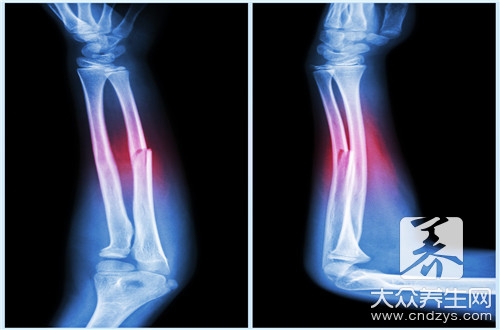

骨折是指骨结构的连续性完全或部分断裂。多见于儿童及老年人,中青年人也时有发生。病人常为—个部位骨折,少数为多发性骨折。经及时恰当处理,多数病人能恢复原来的功能,少数病人可遗留有不同程度的后遗症。

骨折病人的典型表现是伤后出现局部变形、肢体等出现异常运动、移动肢体时可听到骨擦音。此外,伤口剧痛,局部肿胀、淤血,伤后出现运动障碍。

1.复位

是将骨折后发生移位的骨折断端重新恢复正常或接近原有解剖关系,以重新恢复骨骼的支架作用。复位的方法有闭合复位和手术复位。